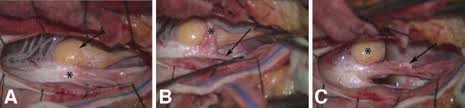

The adult presentation of tethered cord syndrome TCS is well recognized but continues to pose significant diagnostic and management challenges. The tethering effect was caused either by a split cord malformation a thick filum terminale a conus medullaris lipoma with extradural extension or various combinations of these mechanisms. Progressive sensory and motor deficits may affect the legs potentially resulting in numbness weakness or.

Indications techniques and long-term outcomes in. Adult tethered cord is determined by an MRI which shows a low level of the conus medullaris below L2 and thickened filum terminale. The occult tethered cord syndrome and surgical indication - PEDs Neuro Ortho UroGI Progressive Syringohydromelia Filum 2mm in axial section Derm ¾ clinical qualifiers mandatory for surgical indication. In adults symptoms are aggravated by trauma maneuvers associated with stretching of the spine flexion disc herniation and spinal stenosis. J Neurosurg Spine 42123-1312006. The tethering effect was caused either by a split cord malformation a thick filum terminale a conus medullaris lipoma with extradural extension or various combinations of these mechanisms. The authors performed a retrospective study of clinical outcomes after neurosurgical intervention in 60 adults with TCS. Of the 2515 patients 85 adults with a tethered cord syndrome formed the basis of this study. In the present study we analyzed the data of patients who presented with TCS in adulthood with the aim of studying the clinical spectrum and management strategies.